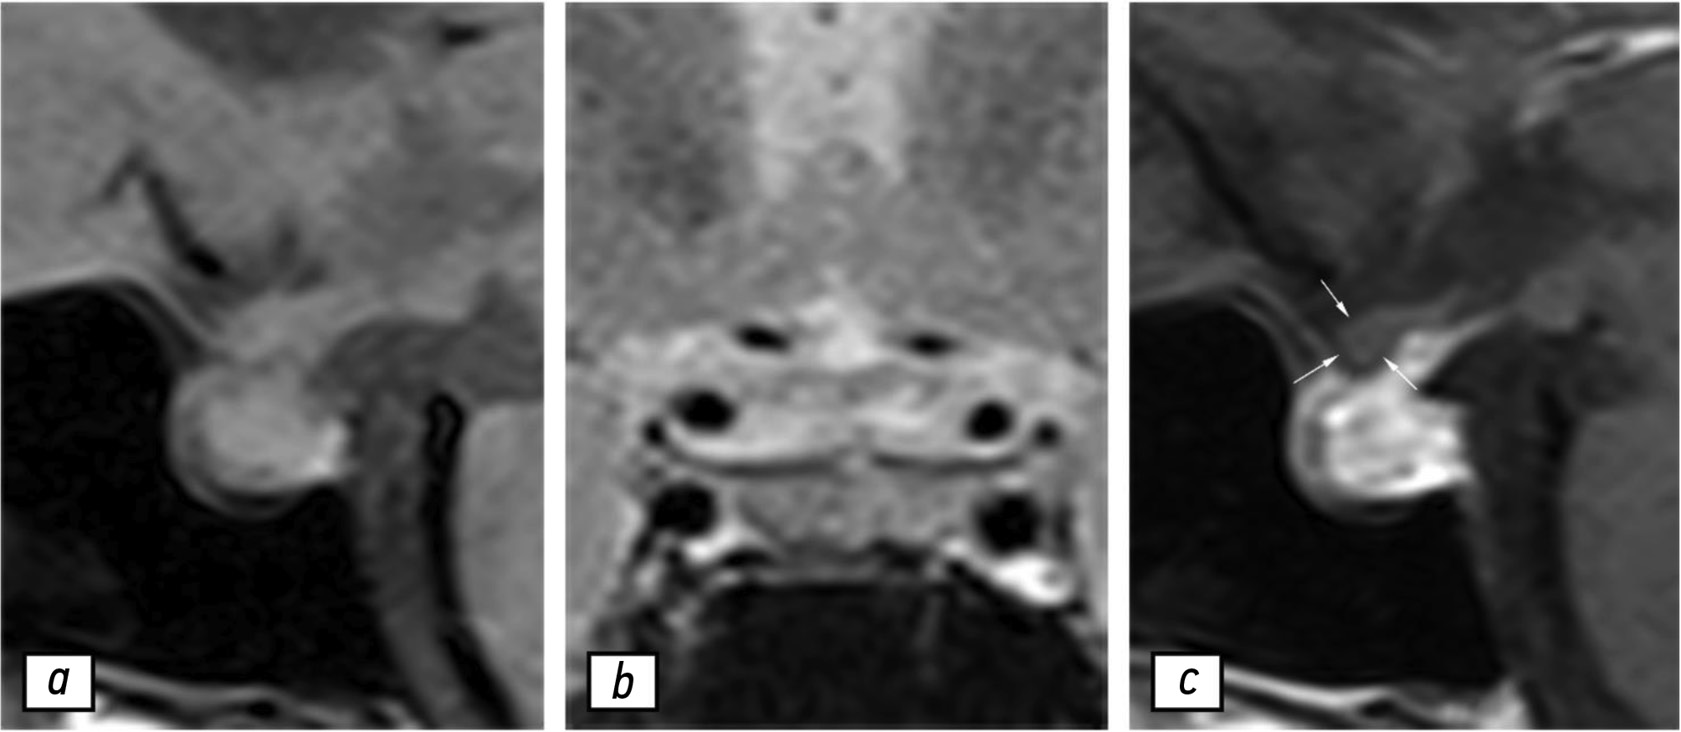

На этом этапе пациентка получала преднизон (утром и вечером — 10 и 5 мг соответственно) и каберголин (0,25 мг два раза в неделю). На фоне лечения состояние пациентки улучшилось. При проведении контрольной МРТ 03.10.2022 выявлено выраженное уменьшение гипофиза и снижение гетерогенности его структуры (рис. 5).

Рис. 5. Результаты магнитно-резонансной томографии гипофиза, 03.10.2022: a — T1-взвешенное изображение в сагиттальной проекции; b — T2-взвешенное изображение в коронарной проекции; с — T1-взвешенное изображение в сагиттальной проекции с контрастированием. Гипофиз не увеличен, в центральных отделах наблюдается гетерогенное накопление контрастного вещества. Хиазма утолщена и имеет умеренно гетерогенную структуру. Отмечены положительные изменения по сравнению с предыдущими данными магнитно-резонансной томографии.